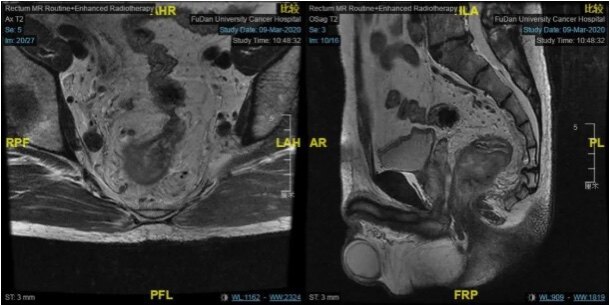

低位直腸癌患者的保肛與否,一文帶您全面思考。 假如你是一名肛腸外科醫(yī)生,現(xiàn)在有這樣一個病例擺在你面前: 患者為40歲男性,初診為腫瘤下緣距離肛門僅有3.5cm的極低位直腸癌,有強烈的保肛和生存意愿。但局部病期較晚,腫瘤累及整個腸圈,并且合并有直腸周圍雙側髂血管旁多發(fā)淋巴結轉移。你會怎么做? 患者放療前 復旦大學附屬腫瘤醫(yī)院大腸外科李心翔教授的“標準答案”公布: 李心翔教授為該患者精心制定了治療方案。首先行術前的新輔助放化療,控制疾病的發(fā)展,經(jīng)治療患者直腸腫瘤及轉移淋巴結明顯縮小。 患者放療后 利用這個有利時機,李教授術前仔細分析病情后,為該患者成功實行腹腔鏡下TaTME(transanal total mesorectal excision)手術及雙側側方淋巴結清掃術(Lateral lymphadenectomy),徹底切除了直腸腫瘤和側方的淋巴結轉移,保住了肛門,并且腹部無切口?;颊咝g后恢復良好,一周后順利出院。 從這個病例其實可以引申出許多臨床問題:什么樣的患者能保肛?能保肛的患者怎樣保肛?TaTME術如何保證“無瘤”原則,降低復發(fā)風險?綜合治療手段在低位直腸癌患者中如何應用?未來我們還應該做些什么?這些都是臨床醫(yī)生亟待思考和解決的問題。 近期,我們也邀請到了李心翔教授為我們詳解TaTME術的臨床應用和低位直腸癌患者的臨床診療手段。 李心翔教授 如何辯證思考準確把握保肛原則 當文首這樣一個病例擺在你面前,你首先想到的是“能不能保肛?”還是“該不該保肛?” 直腸癌手術技術發(fā)展迅速,越來越多的患者在疾病得到良好控制的同時也得到了生活質量的保障。當“能不能保肛”似乎已經(jīng)不成難題,緊接著需要思考的問題又來了:所有患者都應該保肛嗎?有哪些禁忌證?如何把握? 保肛的適應證有以下幾條:腫瘤下緣距齒線>2cm;病理分型為高中分化;腫瘤浸潤深度要在T2期以內(nèi)。同時,術前外括約肌已經(jīng)存在異常、大便失禁、盆底肌功能差、年齡過大或體質過弱的患者都不適合保肛。 保肛其實是一個綜合決策,在于以下三個方面:技術層面、腫瘤學和功能學層面。技術層面已經(jīng)不是難題,醫(yī)生就要對腫瘤學和功能學進行更嚴格的把控。 李心翔教授談到: 有些患者本身肛門功能很差,就算醫(yī)生將腫瘤全部切除,保住外觀,卻保不住功能。我自己也碰到過這樣的一個患者,強烈要求保肛門,我們一再跟他強調保肛術后效果并不理想。但是他保肛意愿強烈,我們也尊重他的意見。 這位患者術后正如我們所預估的,肛門功能經(jīng)過一年兩年的訓練還是很差,最后只能重新接受手術。尤其是直腸癌、高齡的患者,很多本身盆底肌功能就不好,如何在保證功能的情況下也保證腫瘤不會復發(fā)轉移,是需要醫(yī)生考慮的。 另外直腸癌術中的腫瘤切緣應該如何決斷也是醫(yī)生要慎重考慮的問題。腫瘤切緣應該保留多少與病理類型也有密切相關,比如普通患者可能1cm就夠了,甚至化療后加上術中冰凍只需要保留0.5cm的切緣。但是對于特殊的病例類型,比如印戒細胞癌、低分化腺癌、黏液腺癌的患者就需要擴大切除范圍。 “我以前碰到一個印戒細胞癌的患者,腫瘤切緣應擴大到3cm以后,組織病理檢查還是陽性。腫瘤的切緣有限,對于病理類型惡性程度高、復發(fā)可能性大、病期進程晚的患者,醫(yī)生需要擴大切緣范圍。這樣的患者不適合保肛,也不能夠保肛。”李心翔教授補充道。 相輔相成:腹腔鏡輔助TaTME彌補傳統(tǒng)技術難題 雖然目前腹腔鏡技術在直腸癌治療中的保肛中的優(yōu)勢地位已經(jīng)得以體現(xiàn),然而對于極低位直腸癌(距肛緣小于5cm),病灶深入盆腔,尤其是男性患者合并前列腺增生、骨盆腔狹窄、肥胖等因素將會導致手術視野難以充分暴露,導致腫瘤根治效果和保肛概率的降低。 腹腔鏡下TaTME技術可行性和安全性已被證實。該手術采用經(jīng)肛經(jīng)腹的“上下協(xié)助”方式,經(jīng)肛直接從肛緣進入盆底,可以相對容易地完成低位直腸和系膜的完整游離;有效的暴露還有助于保護盆神經(jīng)叢,增加對術后肛門和性功能保留。 此外,常規(guī)經(jīng)腹手術腫瘤的遠側切緣的判斷上,術者既往是通過手術器械碰觸或助手肛診來“經(jīng)驗性”地判斷,有可能導致遠切緣距離不足而增加腫瘤復發(fā)的可能性。而TaTME可經(jīng)肛直視下離斷腫瘤遠端直腸,使得遠切緣更為精確可靠,以保證腫瘤根治效果。 TaTME目前的手術適應證為中低位直腸癌,尤其是低位直腸癌;對于男性、前列腺肥大、肥胖、腫瘤直徑>4 cm、直腸系膜肥厚、低位直腸前壁腫瘤、骨盆狹窄、新輔助放療引起的組織平面不清晰等“困難骨盆”的直腸癌患者。 對此,李心翔教授這樣總結道: 任何一個好的技術,它能夠彌補另外一個技術的一個不足之處。大多數(shù)患者從傳統(tǒng)的腹腔鏡下做是沒有問題的,經(jīng)腹的腔鏡視野也很好。所以TaTME與傳統(tǒng)的經(jīng)腹切除術兩者應該是互補的,可以從技術層面上解決一些問題。 穩(wěn)中求勝:“無瘤”原則必須貫穿始終 雖然TaTME彌補了傳統(tǒng)經(jīng)腹全直腸系膜切除(TME)手術的技術難題,但同時對操作者把握“無瘤”原則的要求、手術本身的難度和風險也更大。由于肛腔本身空間的局限性要求操作者單孔操作,并且“由下而上”的操作路徑首先暴露腫瘤,如何在切除腫瘤的同時嚴格把握“無瘤原則”成了操作者亟待考慮的問題。 李教授補充道:“去年挪威報道了他們國家很多患者在TaTME術后不到一年的時間里腫瘤復發(fā),而且這種復發(fā)跟以往的復發(fā)不一樣,是多點的復發(fā)。因為這樣,挪威停止了TaTME的技術?!? 因此,我們必須嚴格把握“無瘤”原則,盡量在操作的時候不接觸腫瘤。以往我們“從上往下”經(jīng)腹操作,最后才做到腫瘤。TaTME經(jīng)肛操作,首先暴露的就是腫瘤,如果操作不當或者操作失誤,就會導致腫瘤物理性的種植,進一步對患者造成危害。所以操作者必須操作嚴謹,并且接受過規(guī)范化培訓。 綜合治療:為患者創(chuàng)造最大獲益 回歸到病例本身,患者在術前接受了新輔助放化療,疾病發(fā)展得到良好控制,為后續(xù)手術創(chuàng)造條件。手術除了TaTME以外同時進行了側方淋巴清掃。綜合治療手段在這個患者的診療過程中得到了集中體現(xiàn)。 但是面對進展期直腸癌,單純靠外科技術是遠遠不夠的,如何真正提高患者的五年生存率?如何降低局部復發(fā)率?這個時候,綜合治療的手段就顯得至關重要。 李心翔教授談到:術前新輔助放化療的價值在很多臨床試驗研究中都已經(jīng)非常明確地被肯定。近幾年,新輔助化療的價值更加突顯。有研究表明放療會增加直腸癌患者術后吻合口瘺等并發(fā)癥的發(fā)病風險。對于中高位直腸癌的患者,我們也可以提倡用新輔助化療來代替新輔助放化療。 對于高危的、低位的直腸癌患者,推薦使用直腸癌全程新輔助治療(TNT)的模式?!靶g前將新輔助化放療做足,使腫瘤盡可能退縮,最后實施手術,手術后一般不再追加化療。TNT的病理學完全緩解(pCR)率能夠達到30%以上,也就是說100個直腸癌患者中,30個可以完全避免進行手術。對于TNT結束后達到pCR的患者,就可以采用新的W&W政策(watch & wait,觀察并等待)?!崩罱淌诮庾x道。 所以綜合治療手段不僅僅能夠降低局部復發(fā)率,同時也為低位保肛患者提供新的治療模式和手段。 在對于側方淋巴結清掃術的適應證把控上,李心翔教授也強調: 因為側方淋巴清掃術存在一定的風險,容易造成神經(jīng)的損傷,所以不要過度清掃。根據(jù)專家共識,我們不主張預防性的側方淋巴清掃,還是應該以治療性為主,比如腫瘤組織大小超過1cm或者懷疑淋巴結轉移的。臨床醫(yī)生要避免對患者進行過度治療,造成不必要的傷害。 思考不止:“技術的可行性,不代表治療的合理性” 當?shù)臀恢蹦c癌的外科技術飛速發(fā)展,當技術的瓶頸被逐漸突破,當醫(yī)生能力越來越強大,治療的合理性應該被更慎重地考慮。 李心翔教授表示:“在張忠濤院長帶領下,全國各地的專家成立了一個TaTME的數(shù)據(jù)管理庫,基于中國數(shù)據(jù),在未來有序推廣TaTME,形成中國的TaTME臨床指南。” 相信在未來,更多中國特色的直腸外科技術的創(chuàng)新與直腸癌規(guī)范化綜合治療會出現(xiàn),低位直腸癌患者能夠獲得更好的生活質量與更長的生存期。 參考文獻: [1]2020中國臨床腫瘤學會(CSCO)結直腸癌診療指南 專家簡介: 李心翔,主任醫(yī)師、教授、博士生導師 復旦大學附屬腫瘤醫(yī)院大腸外科主任醫(yī)師 上海市抗癌協(xié)會腫瘤微創(chuàng)專委會腔鏡外科學組組長 上海市抗癌協(xié)會胃腸腫瘤腹腔鏡專業(yè)委員會主任委員 中國臨床腫瘤學會(CSCO)理事 CSCO腫瘤微創(chuàng)外科專委會副主任委員 CSCO結直腸癌專家委員會委員/CSCO結直腸癌診療指南執(zhí)筆人 中西醫(yī)結合學會普外專委會直腸癌防治專家委員會主任委員 中國醫(yī)師協(xié)會結直腸腫瘤專委會腹腔鏡專委會副主任委員 中國醫(yī)師協(xié)會肛腸醫(yī)師分會微創(chuàng)與內(nèi)鏡專委會副主任委員 中國研究型醫(yī)院學會結直腸肛門外科專委會副主任委員 中國醫(yī)師協(xié)會肛腸醫(yī)師分會常委 中國醫(yī)師協(xié)會外科分會TaTME專業(yè)委員會常委 本文轉自:醫(yī)學界腫瘤頻道